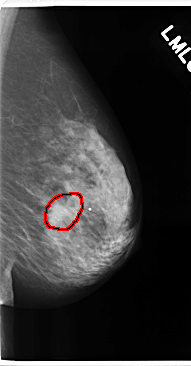

C_0175_1.LEFT_MLO

LEFT_MLO LINES 4752 PIXELS_PER_LINE 2472 BITS_PER_PIXEL 12 RESOLUTION 50 OVERLAY

FILE: C_0175_1.LEFT_MLO.OVERLAY

TOTAL_ABNORMALITIES 1

ABNORMALITY 1

LESION_TYPE MASS SHAPE ROUND MARGINS SPICULATED

ASSESSMENT 5

SUBTLETY 5

PATHOLOGY MALIGNANT

TOTAL_OUTLINES 1

BOUNDARY